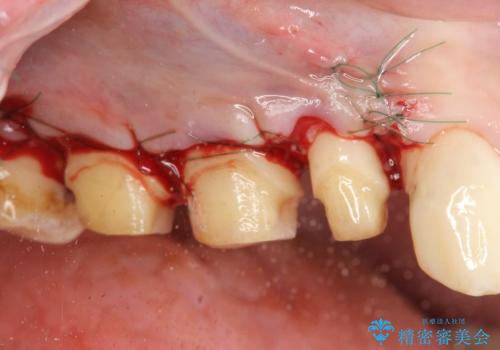

歯周外科で達成する安定したクラウン周囲の歯肉環境

高さが短くなってしまった歯は、安定したクラウンを作るのが難しいため歯ぐきを下げる歯周外科を行ったのちに強度に優れるフルジルコニアクラウンで補綴治療を行います。

すり減ってしまった歯に対し、歯冠長延長術(歯周外科)を行うことで安定したクラウンを製作・装着することが出来ました。

- 外科手術のため、術後に出血、痛みや腫れ、違和感を伴います